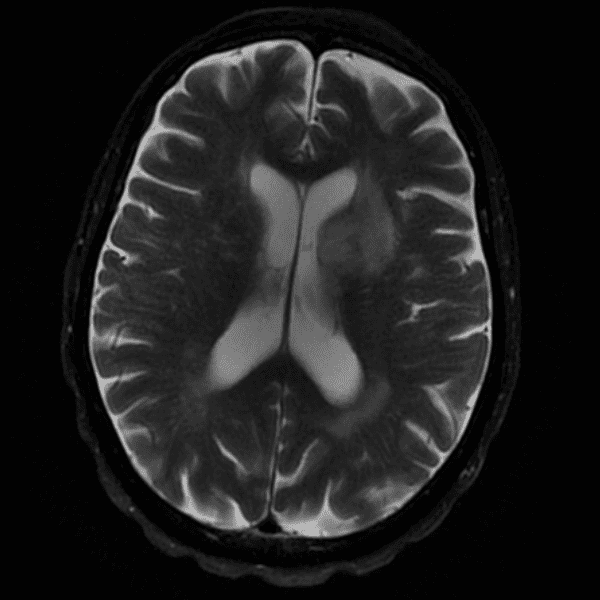

Classic Cases